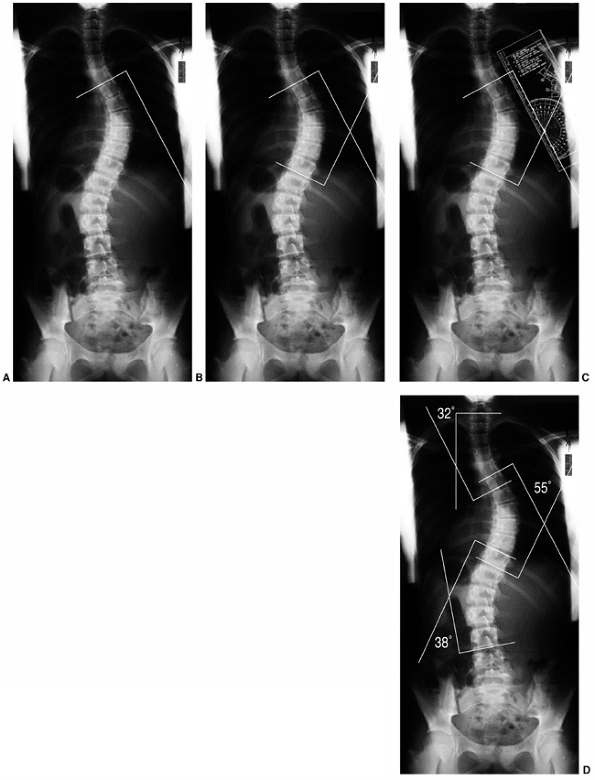

Figure 18.14 A:

Measurement of the Cobb angle. The end vertebrae of each curve must be selected before any measurement can be made. The end vertebrae of the curve are those which are most tilted from the horizontal. B: The endplates of the superior and inferior end vertebrae of the thoracic curve are marked on this figure. Perpendicular lines are constructed. C: The angle between the two lines is measured with a protractor and defined as the Cobb angle measure of the scoliosis. D: This method is used for quantifying the magnitude of scoliosis at each of the three regions: upper thoracic, main thoracic, and lumbar.  |